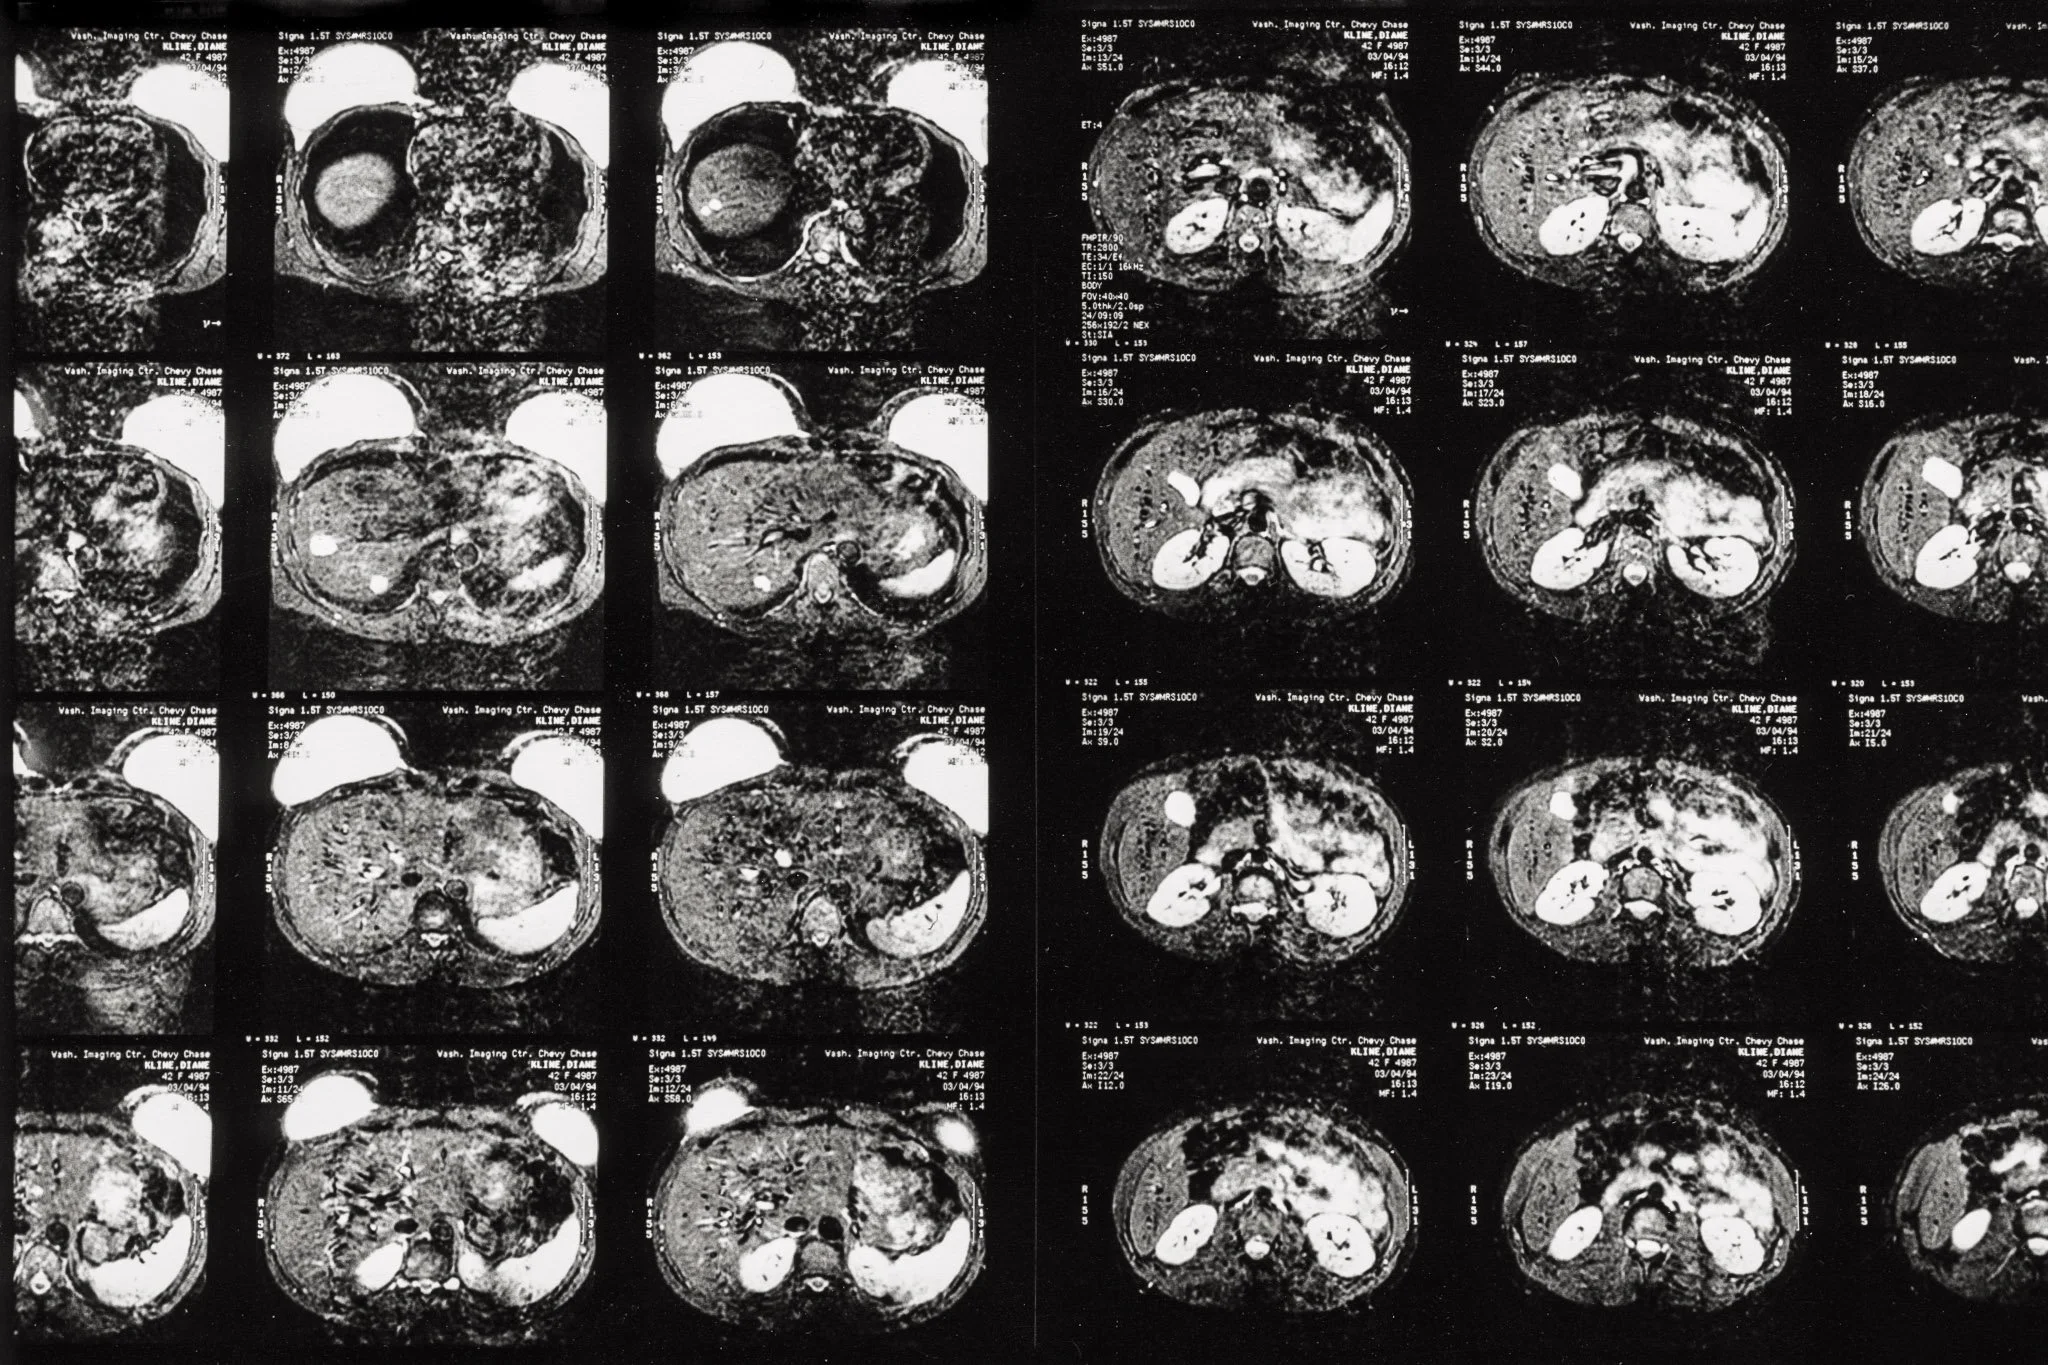

Images from an MRI scan following a recurrence of breast cancer. They are slices of the abdomen near the breast, the breasts mostly opaque as they are saline implants.